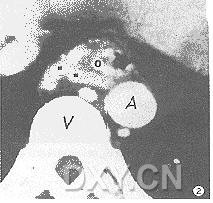

3.腹部CT 可確定肝硬化的存在、肝萎縮的程度和腹水的有無。造影CT 檢查可發現與十二指腸壁相連的異常擴張的血管,出血期可確定造影劑有無從血管外漏。